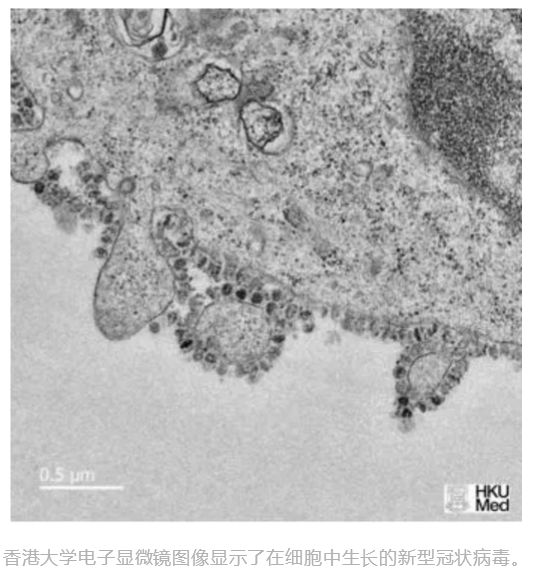

此次武汉发现的新型冠状病毒2019-nCov是一种以前尚未在人类中发现的新型病毒。2019-nCov呈球状,直径约为100~160nm。病毒颗粒由蛋白质和核酸组成:最外面的刺突蛋白(Spike,S)对维持病毒颗粒形态非常重要;再往里是E和M蛋白,这些是撑起病毒颗粒形状的重要蛋白;最里面是其遗传物质RNA,被N蛋白包裹并保护着。

据媒体报道,香港大学研究人员于1月31日公布首批新型冠状病毒在细胞内复制过程的图像。研究人员表示,每个受病毒感染的细胞会衍生出逾千粒病毒粒子,从而继续感染新细胞。